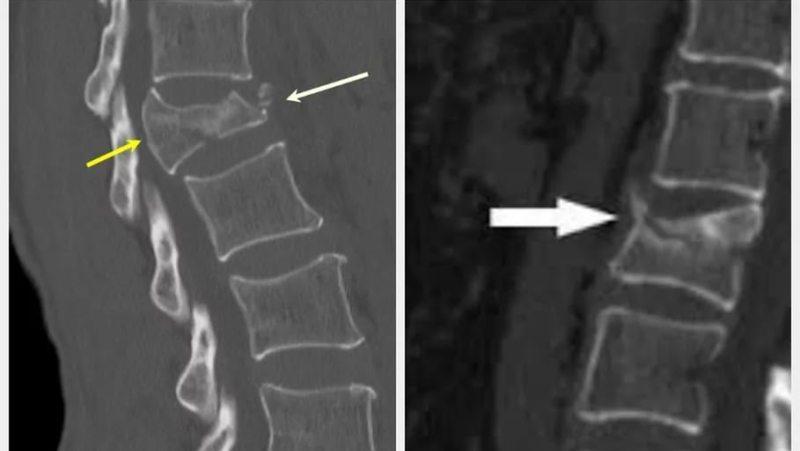

- рентгенография поврежденного участка в двух трех проекциях;

- КТ и МРТ, позволяющие уточнить детали травмы и требуемые при оскольчатом либо компрессионном переломах позвоночника шейного отдела.